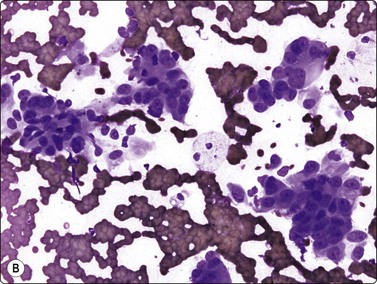

Fig. 10.27 Cholangiocarcinoma

(A) Disorganized clusters of irregular but not very pleomorphic tumor cells with pale cytoplasm and relatively small nuclei (MGG, HP); (B) Disorganized cluster of mildly pleomorphic epithelial cells with hyperchromatic nuclei and prominent nucleoli (MGG, HP); (C) Corresponding tissue section (H&E, IP).

Criteria for diagnosis (Fig. 10.27)172

Sheets, clusters and microglandular arrangement showing nuclear crowding and overlapping,

Decreased cell cohesion,

Small to medium cuboidal/columnar cells resembling bile duct epithelium,

Variable nuclear enlargement and pleomorphism,

Prominent nucleoli in the less well-differentiated tumors,

Delicate cytoplasm with fine vacuolization, positive for mucin,

Occasionally fragments of stroma.

Cholangiocarcinomas often have abundant, desmoplastic stroma and may prove difficult to sample by FNA, or CNB for that matter. Although cells from a well-differentiated cholangiocarcinoma may not appear too different from bile duct epithelium, hepatocytes are absent and the number and size of epithelial sheets are larger than are usually obtained from non-neoplastic liver tissue (Fig. 10.27A). The application of P53, bcl-2 and Ki-67 has been reported as useful in discriminating between them.173 Less well-differentiated carcinomas are indistinguishable from metastatic adenocarcinoma (Fig. 10.27B), particularly those of pancreatic origin. Unfortunately, they are both generally positive for CK7 and CK19 and negative for CK20.174 Distinction from HCC relies on adenocarcinoma showing positivity for mucin and diffuse cytoplasmic staining for CK7, CK19 and pCEA and HCC staining for alpha fetoprotein and HepPar-1 and others as described earlier in the section on HCC.